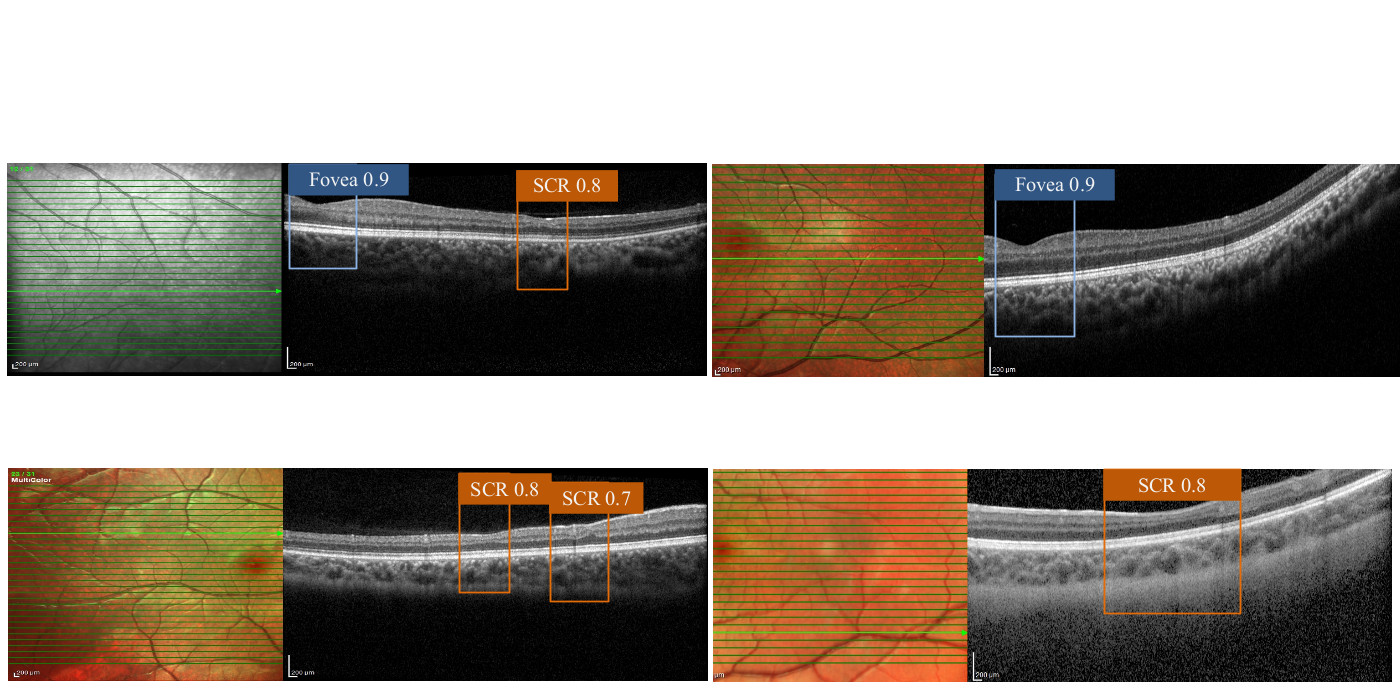

Under microscopy, a cross-section of a human retina shows ten distinct layers. An OCT examination produces a sequence of retinal cross-section images or b-scans. The visibly thin areas on the OCT color-coded retinal thickness map appear as blue or magenta patches where the normal retina is colored green-yellow. The retina has a structure with symmetrically thin inner layers called the fovea. A fovea is a naturally occurring depression in the inner retinal surface, about 1.5mm wide, responsible for visual acuity. The aparrent thickness of the retinal layers play a huge role in diagnosing retinal diseases. At VIMS lab, we focus on analyzing the OCT scans to perform retinal layer segmentation (RLS) and SCR detection (see Research).

Analyzing Adjacent B-Scans to Localize Sickle Cell Retinopathy in OCTs

A deep learning system for sickle cell retinopathy detection using retinal OCT images from children with sickle cell disease